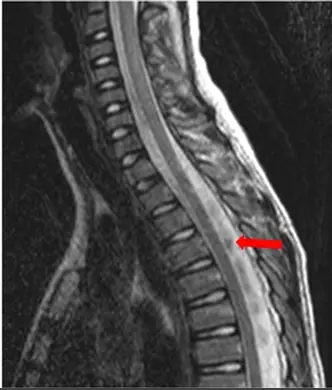

9歲男性。下圖為其 T2加權影像。箭頭所指其最適當的診斷為何?

- 造影參數:這是一張脊髓的矢狀面(Sagittal)T2 加權磁振造影影像。影像中,正常的腦脊髓液(CSF)呈現明亮的高訊號,而脊髓與椎間盤呈現中等訊號。

- 解剖特徵:脊髓(Spinal cord)本身的訊號均勻,外觀粗細正常,沒有任何不正常的腫大、受壓迫或內部訊號改變的跡象。

- 病灶特徵:紅色箭頭指向胸椎段脊髓背側(dorsal)的蜘蛛膜下腔。在此明亮的 CSF 空間中,出現了一塊不規則、邊界模糊的低訊號區(hypointense area)。此低訊號區並未對前方的脊髓造成任何壓迫(無腫塊效應 mass effect),且明確位於脊髓之外。

綜合上述影像分析,該區域的低訊號侷限於脊髓背側的蜘蛛膜下腔,無腫塊效應且脊髓實質訊號正常。這是磁振造影物理學中典型的腦脊髓液流動假影(CSF flow artifact)。這種假影經常出現在頸胸椎交界或胸椎背側,是因為腦脊髓液的複雜脈動造成 MRI 訊號去相位所致。因此正確答案為 (A)。